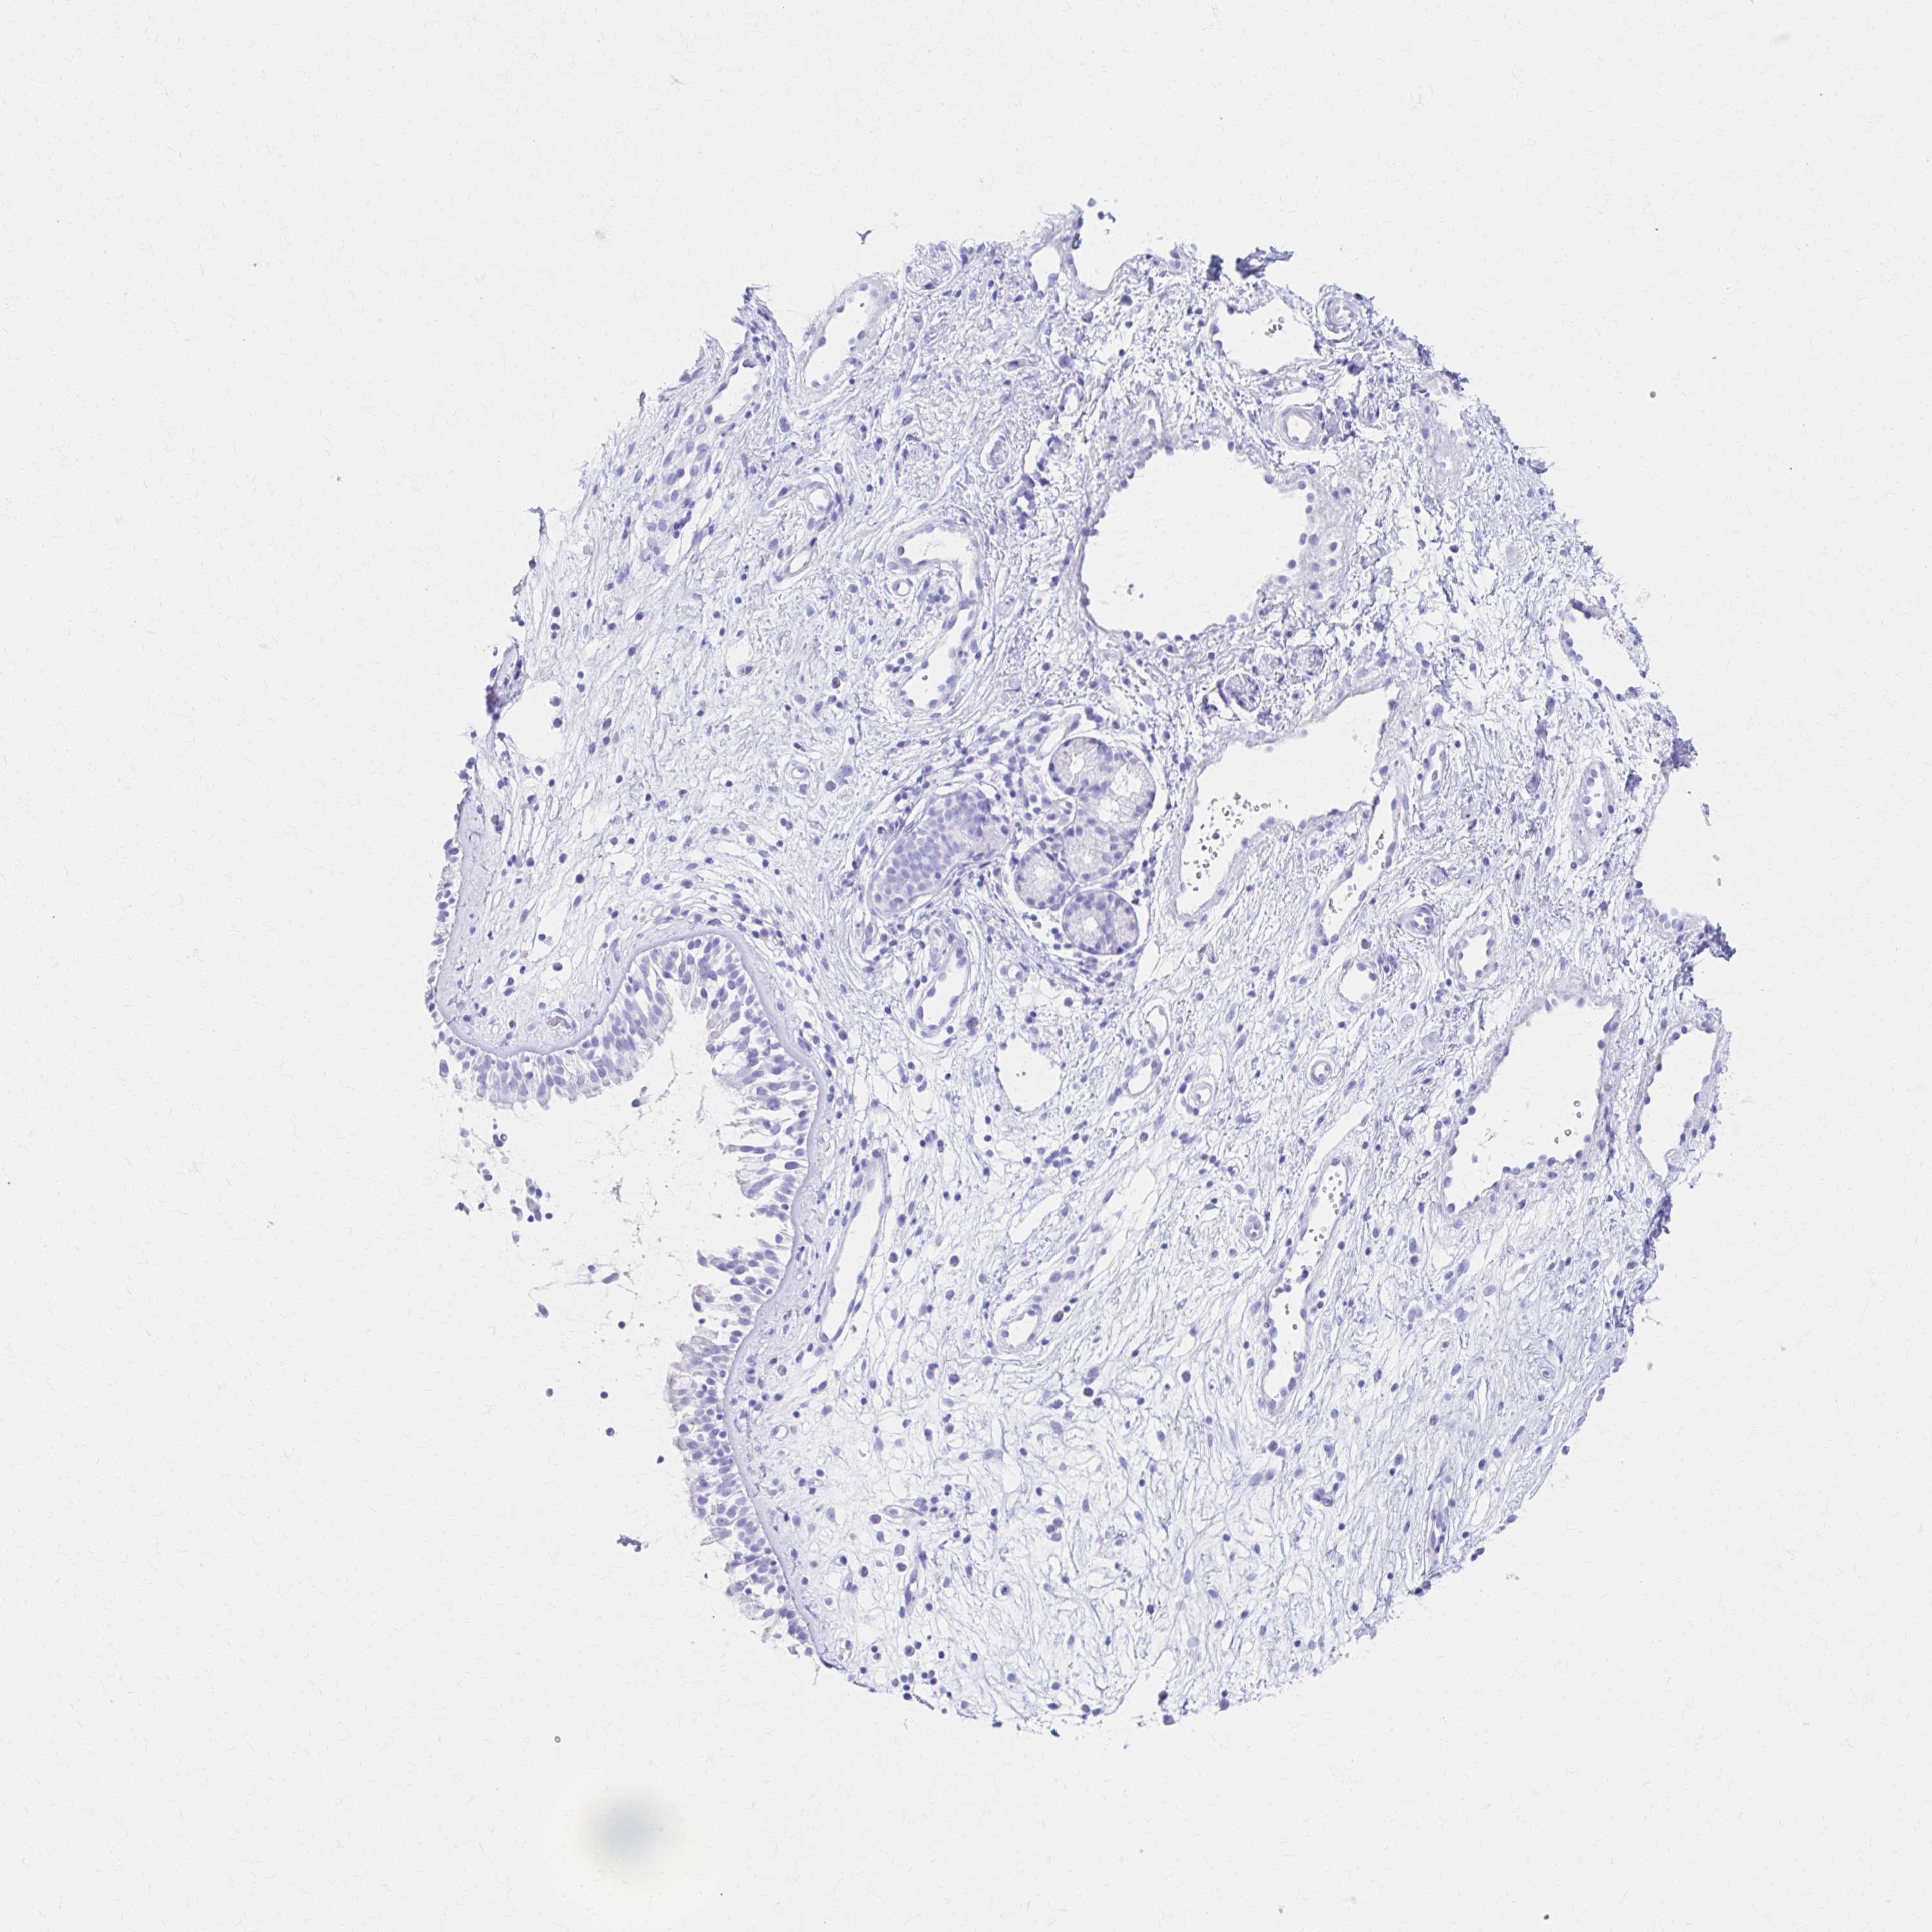

PRKCG